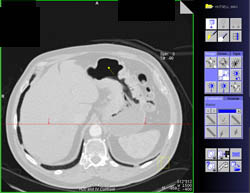

943

Tumor Duodenum Obstructs the Stomach

2,029